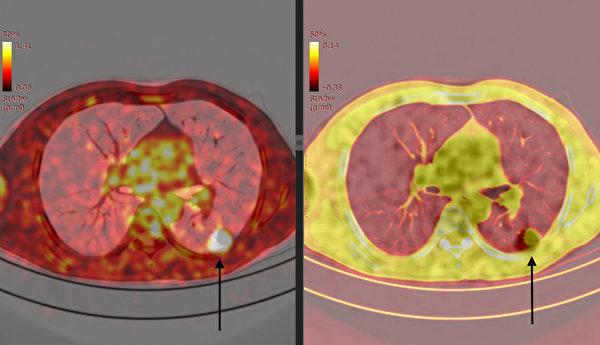

【大紀元2021年06月10日訊】(大紀元記者李少維編譯報導)一份新研究稱,注射COVID-19疫苗後進行PET(正電子斷層掃描顯像)掃描,很容易出現假陽性的結果。這份研究檢查的對象注射的是輝瑞(Pfizer)和莫德納(Moderna)這兩種疫苗。

PET是當前國際上廣泛採用的掃描診斷技術,精確度比MRI和CT更高,可以發現非常小、即很早期的腫瘤病灶。掃描前患者需要注射放射性檢查藥劑(FDG),成分類似葡萄糖水。其檢查的基本原理是,因為癌細胞繁殖迅速,對葡萄糖的消耗量可達正常細胞的好幾倍,所以如果發現藥劑被身體哪個部位吸收量較多,就說明那個地方可能有異常腫瘤。

這份研究發現,在注射過輝瑞和莫德納疫苗後24天內進行PET檢查的病人中,有10.4%的人出現了假陽性的檢查結果。這些假陽性的病灶都在和接受疫苗注射的身體同一側出現。